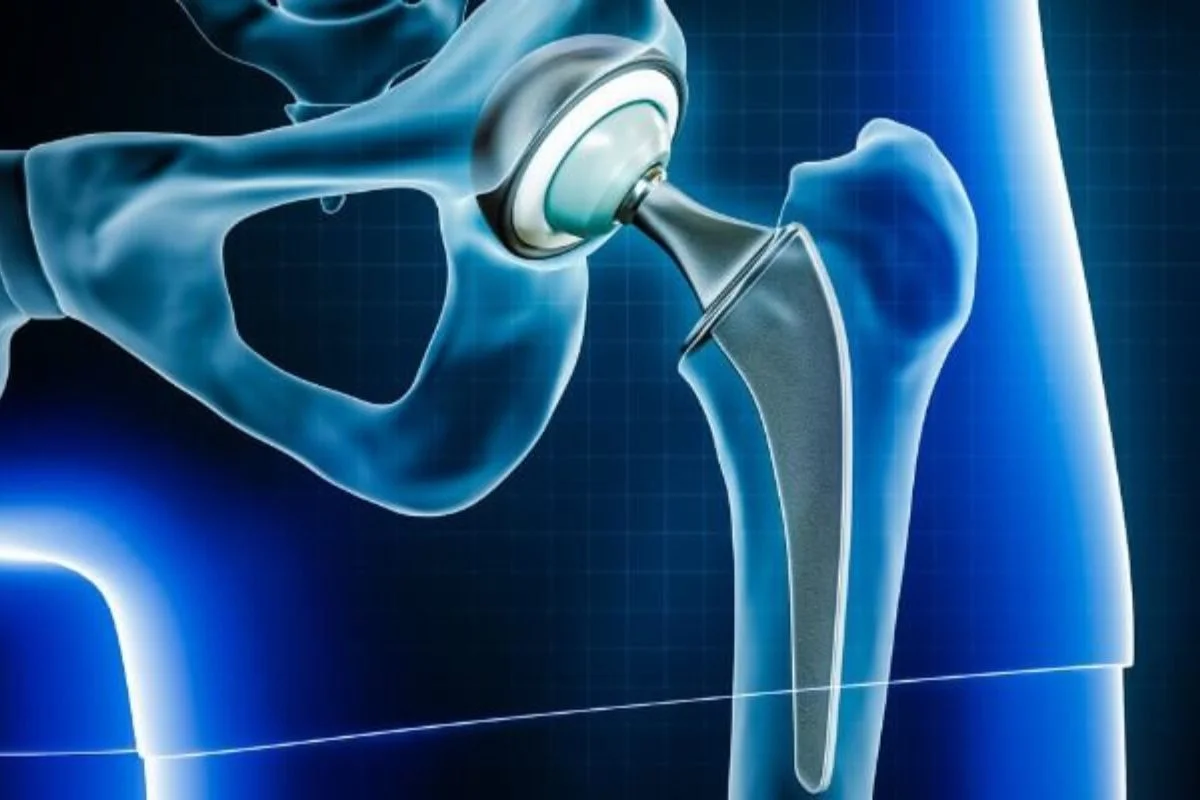

Total hip replacement surgery for degenerative hip disease, arthritis or trauma.